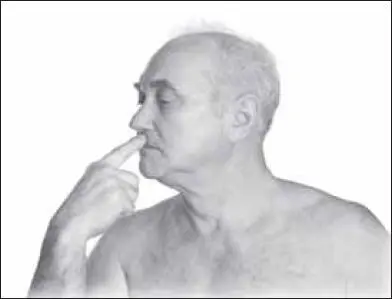

Чтобы предотвратить обморок, надо начинать с массажа точки жэнъ-чжун (расположена на средней линии лица в верхней трети желоба верхней губы) (рис. 135).

Воздействие стимулирующее, тонизирующее, возбуждающее (от 10–20 секунд). Чаще проводится 2-м пальцем (1-м и 3-м пальцем производят фиксацию тканей вокруг точки).